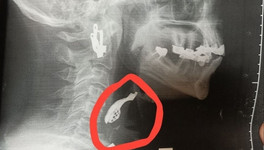

В Кировской области подвели итоги масштабной диспансеризации: с начала года почти 450 тысяч жителей региона прошли профилактические осмотры. Из них более 92 тысяч человек (почти каждый третий) были направлены на второй, углублённый этап обследований.

Главный результат — раннее выявление опасных заболеваний. Медики обнаружили более 15,8 тысяч случаев болезней, о которых люди не подозревали. Среди них — 436 случаев онкологии, почти 1,4 тысячи случаев диабета и свыше 7,7 тысяч заболеваний сердечно-сосудистой системы.

Фото: минздрав Кировской области